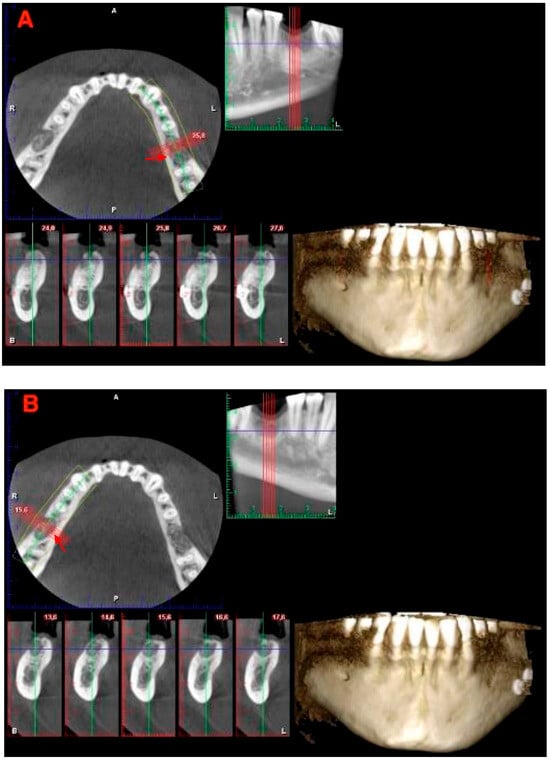

2. Materials and Methods

2.1. Surgical Protocol